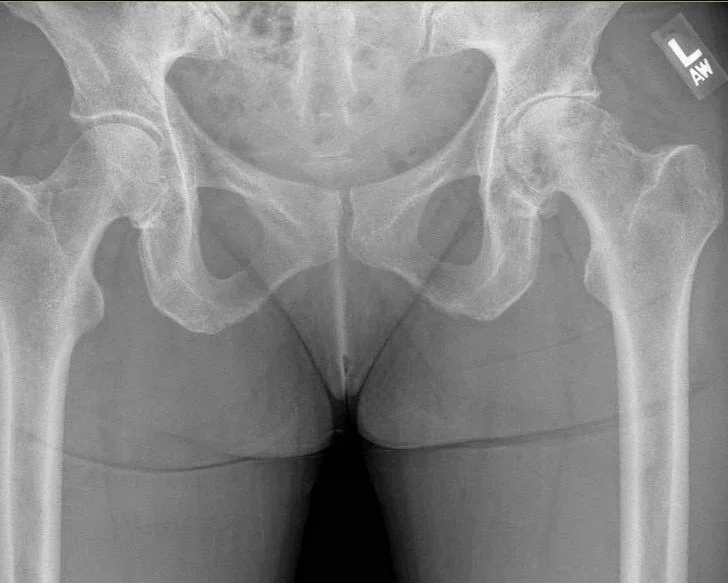

Useage of X Ray Intraop: Easy to get a perfect AP x ray during surgery which allows for more accurate placement of components in the ideal position